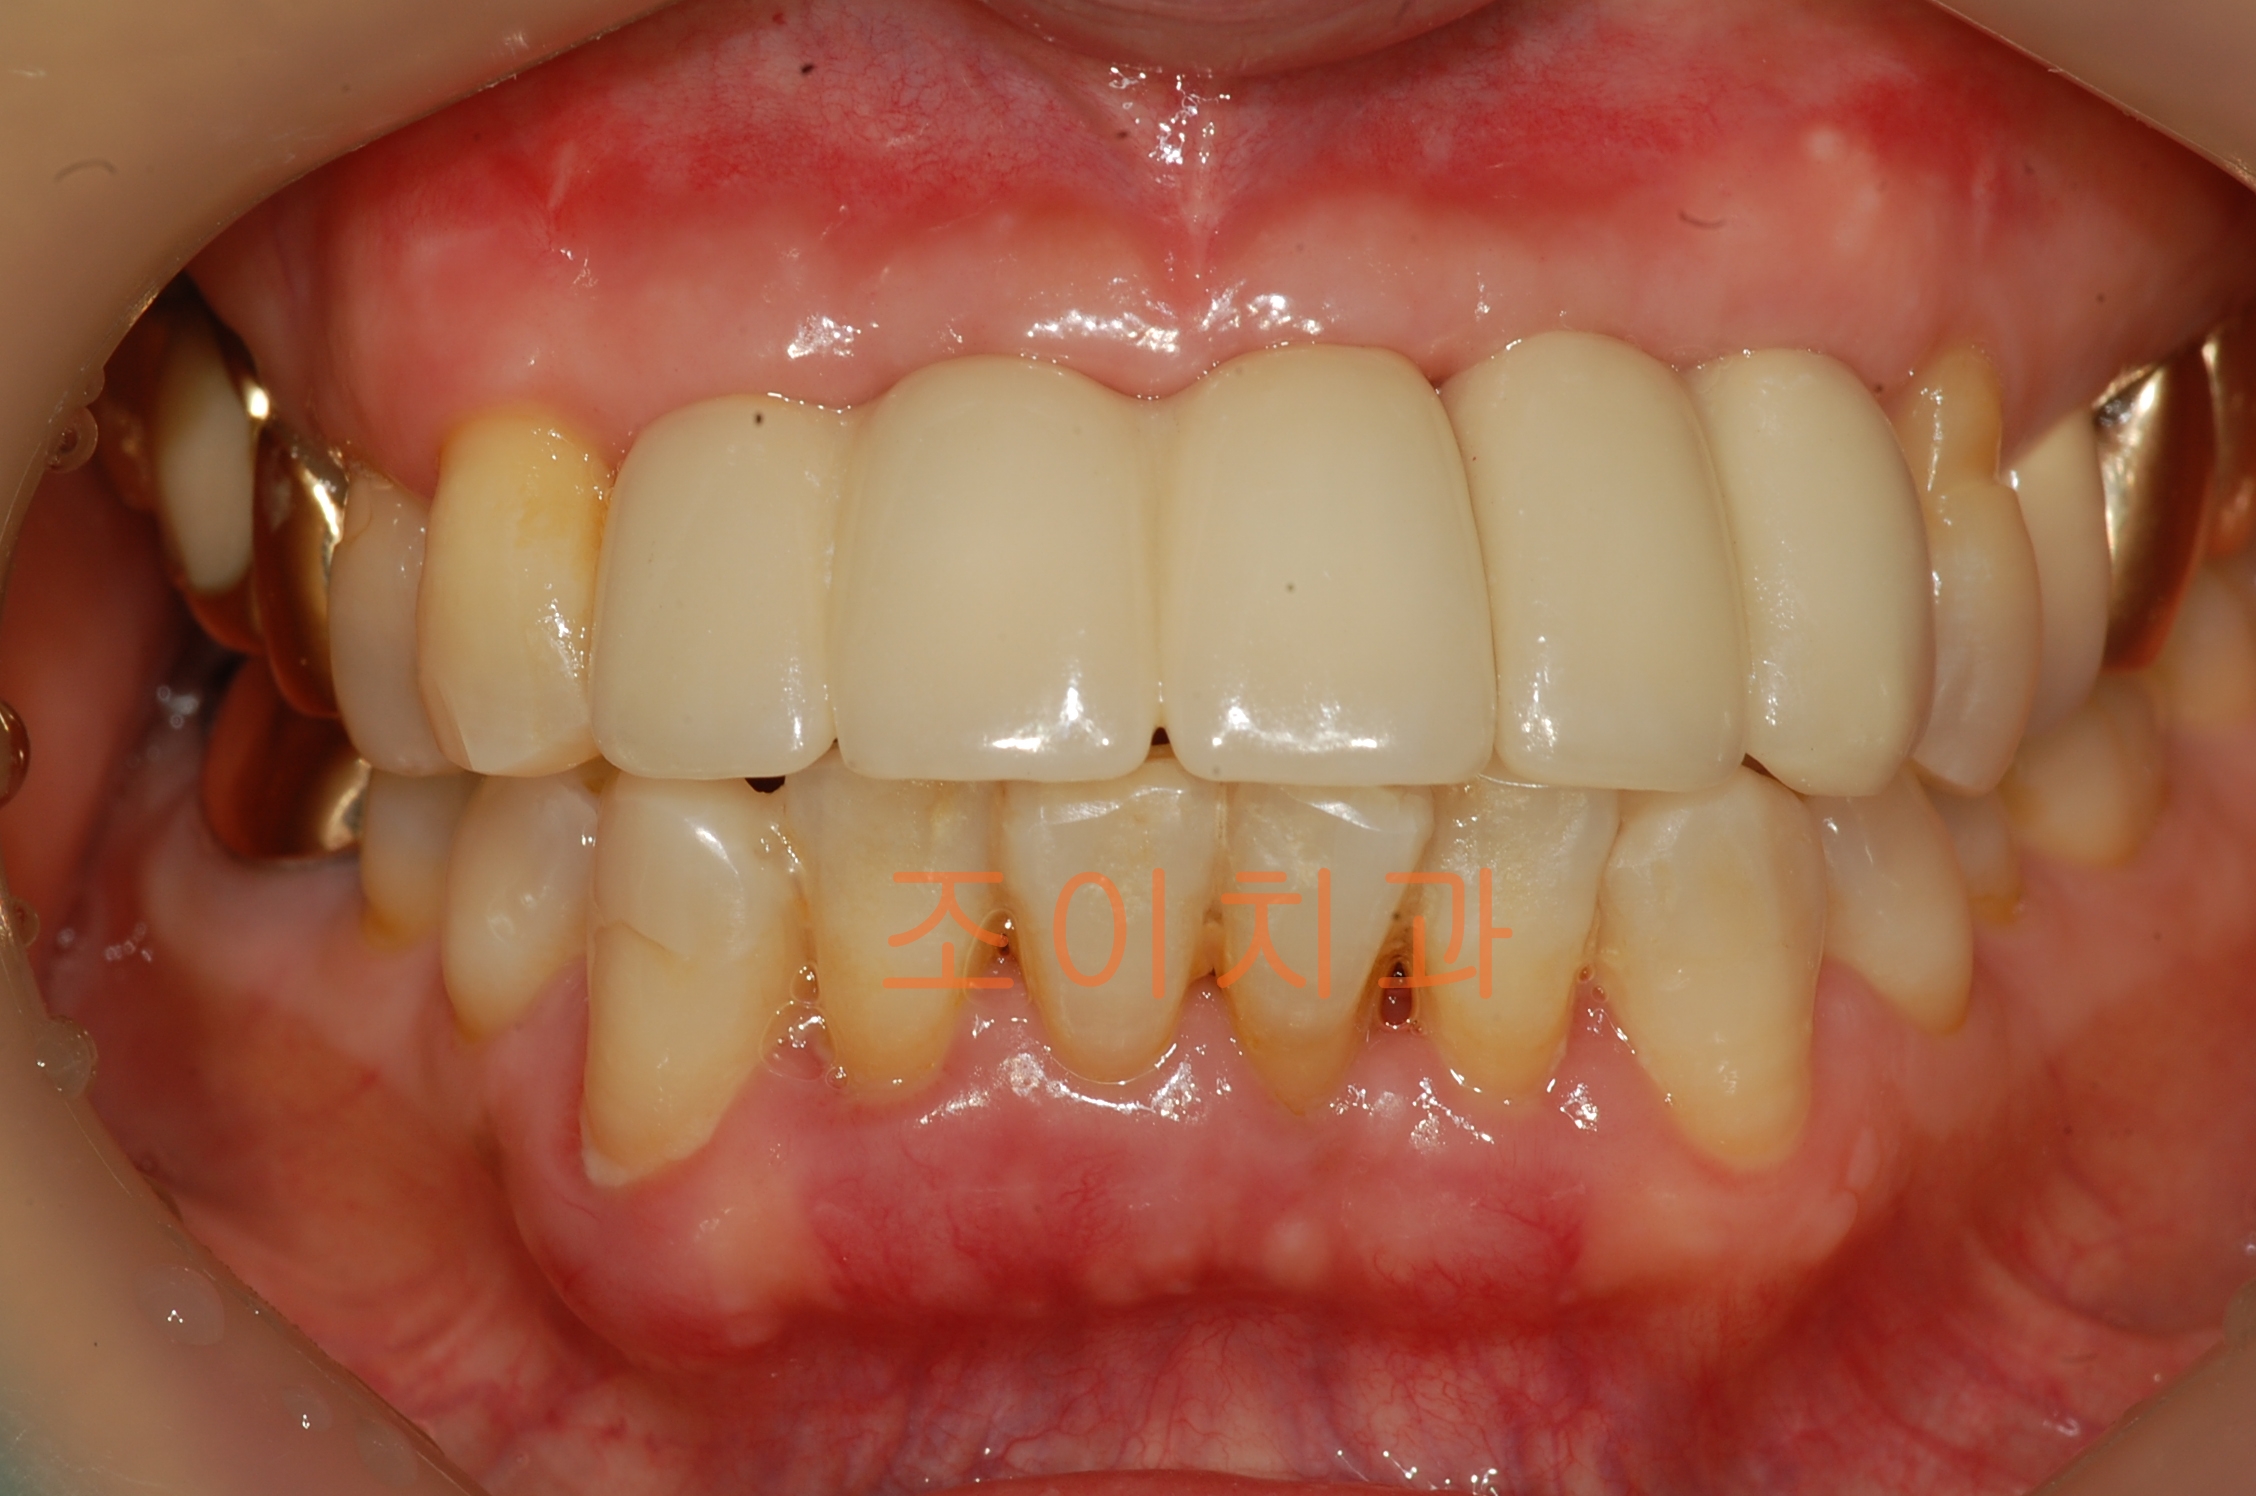

[임플란트] 제목 : 상악전치

임플란트 보철